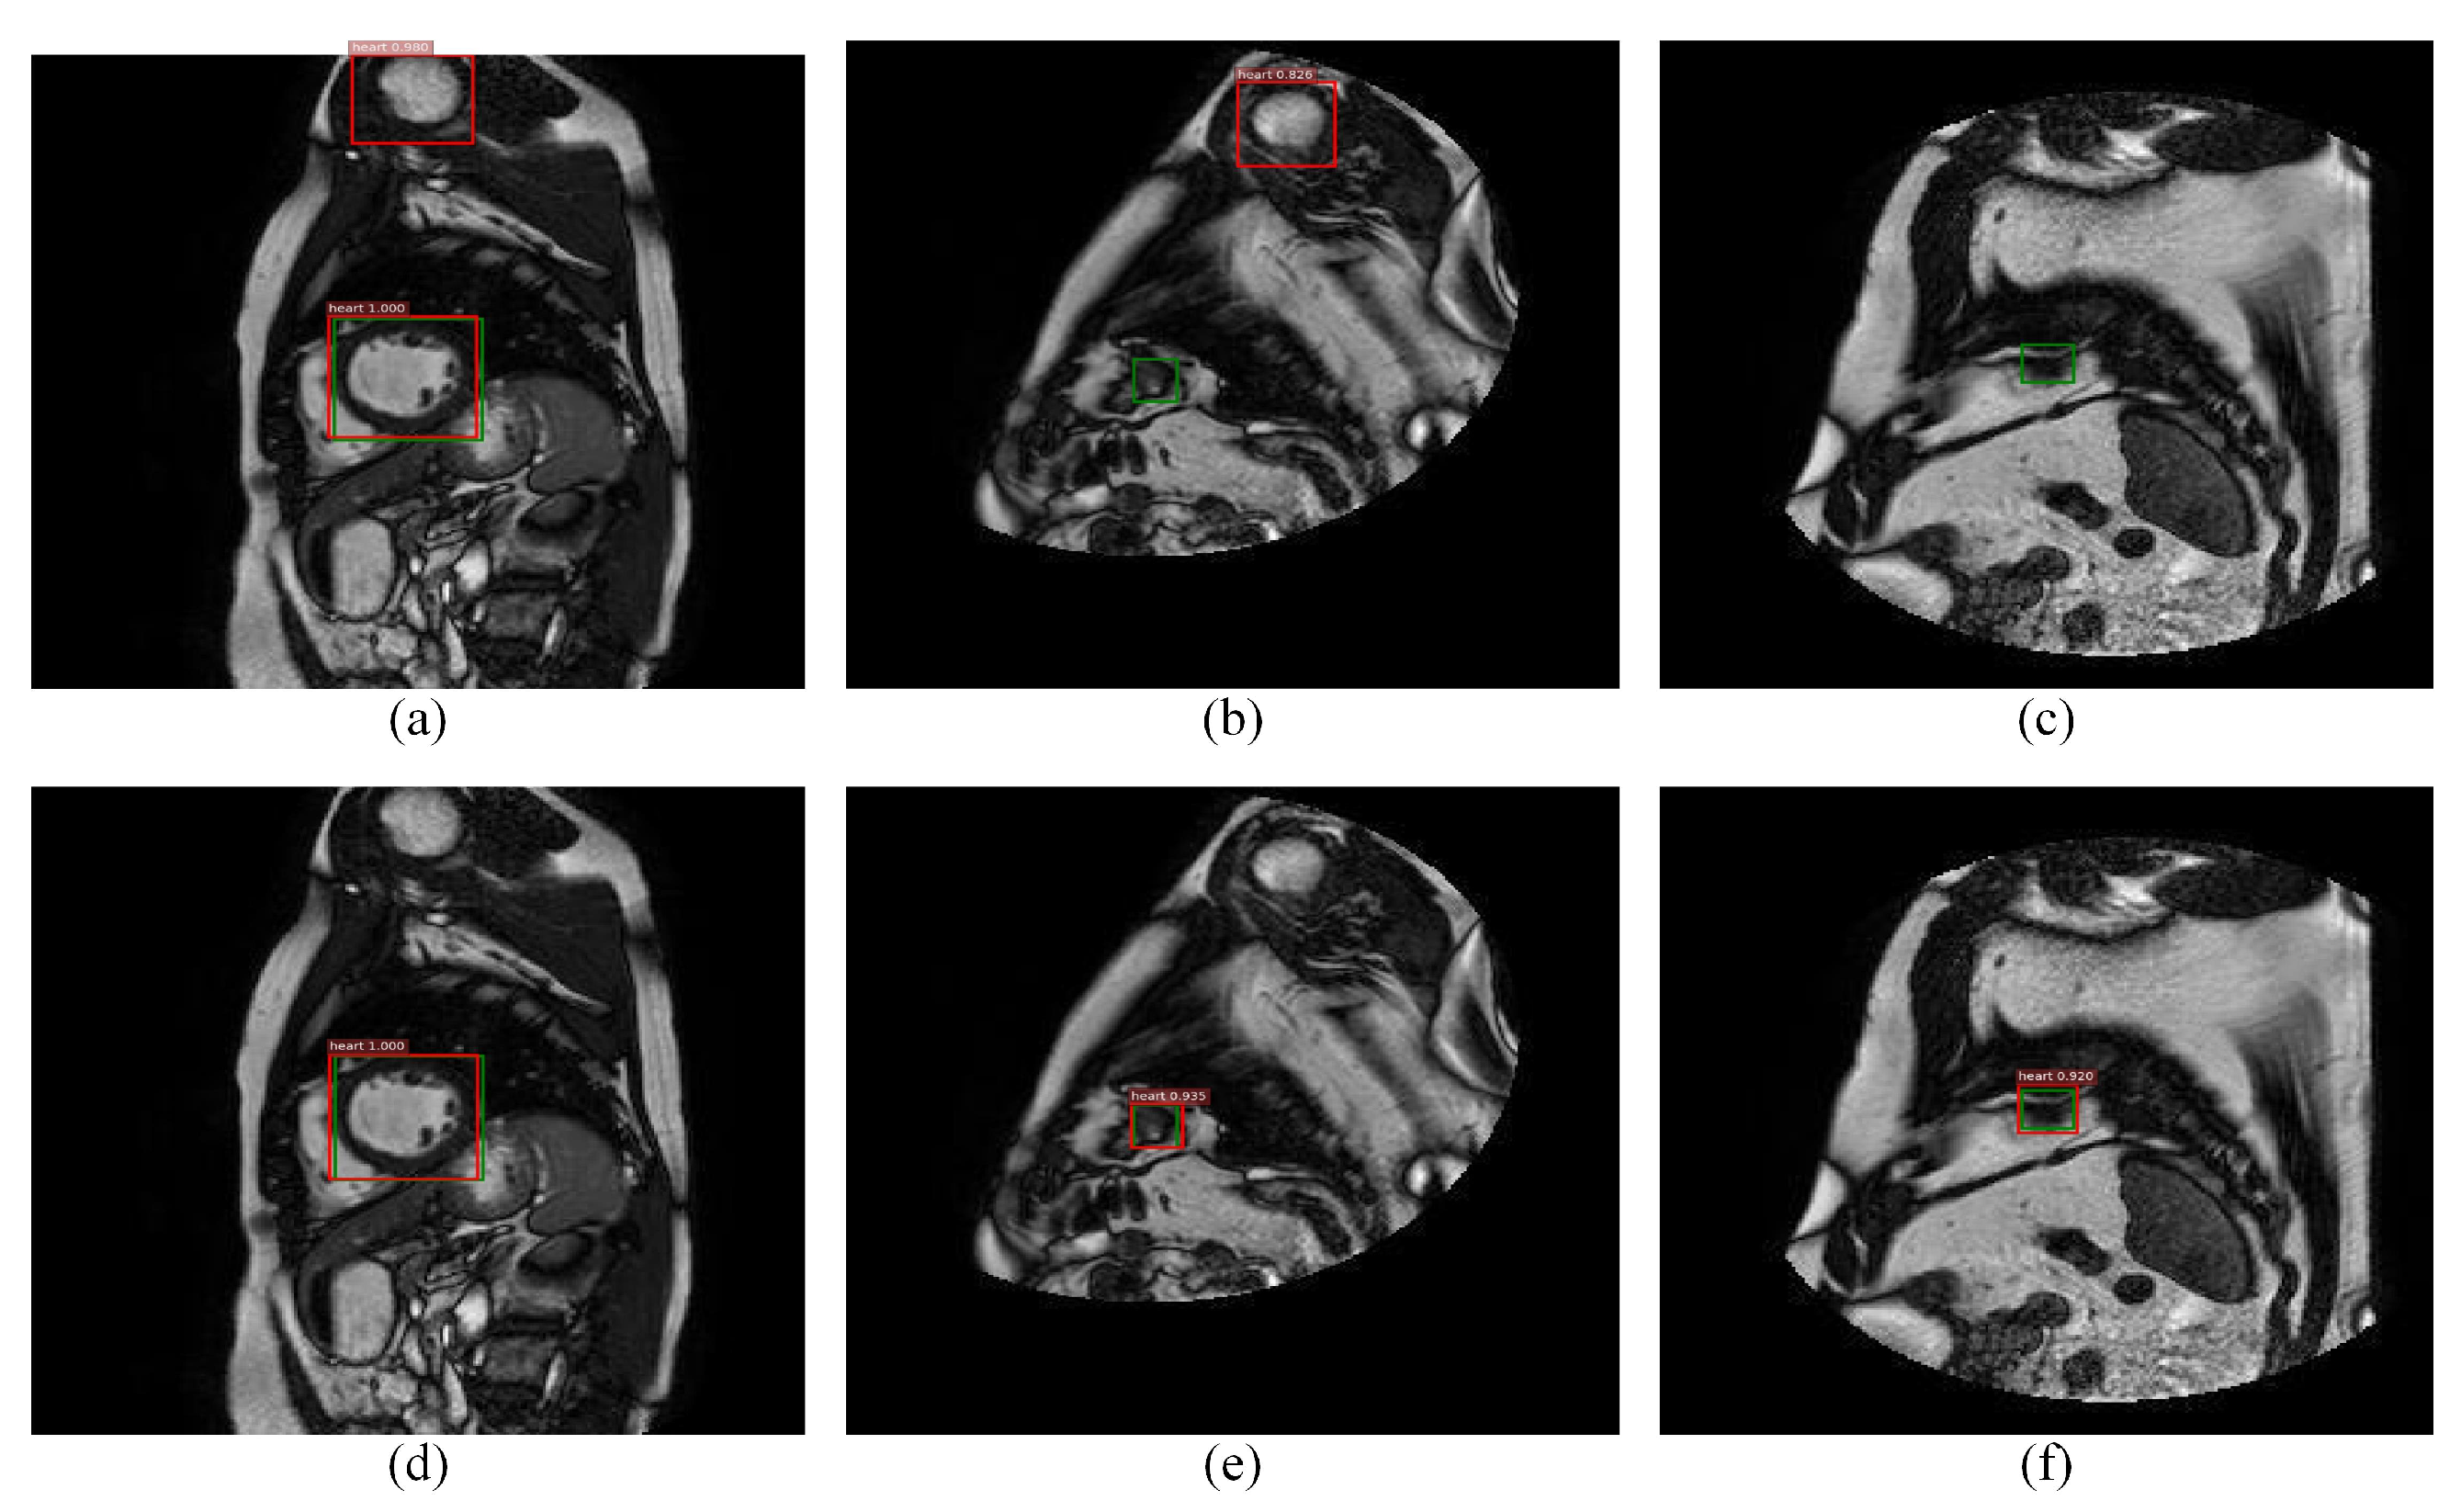

Among the classical two-stage detection algorithms, Faster RCNN shows state-of-the-art performance. However, it has certain limitations when it is directly applied to cardiac MRI left ventricle detection. Figure 1 reports some examples of error detection and the possible reasons are mainly due to the following three points:

Detection examples of hard false positives and hard false negatives samples, where the first row (a–c) and the second row (d–f) are the results of Faster RCNN and the proposed method, where red and green denotes the detection rectangle and the ground truth in each image, respectively. It is seen that pseudo or small left ventricles easily lead to misdetection.